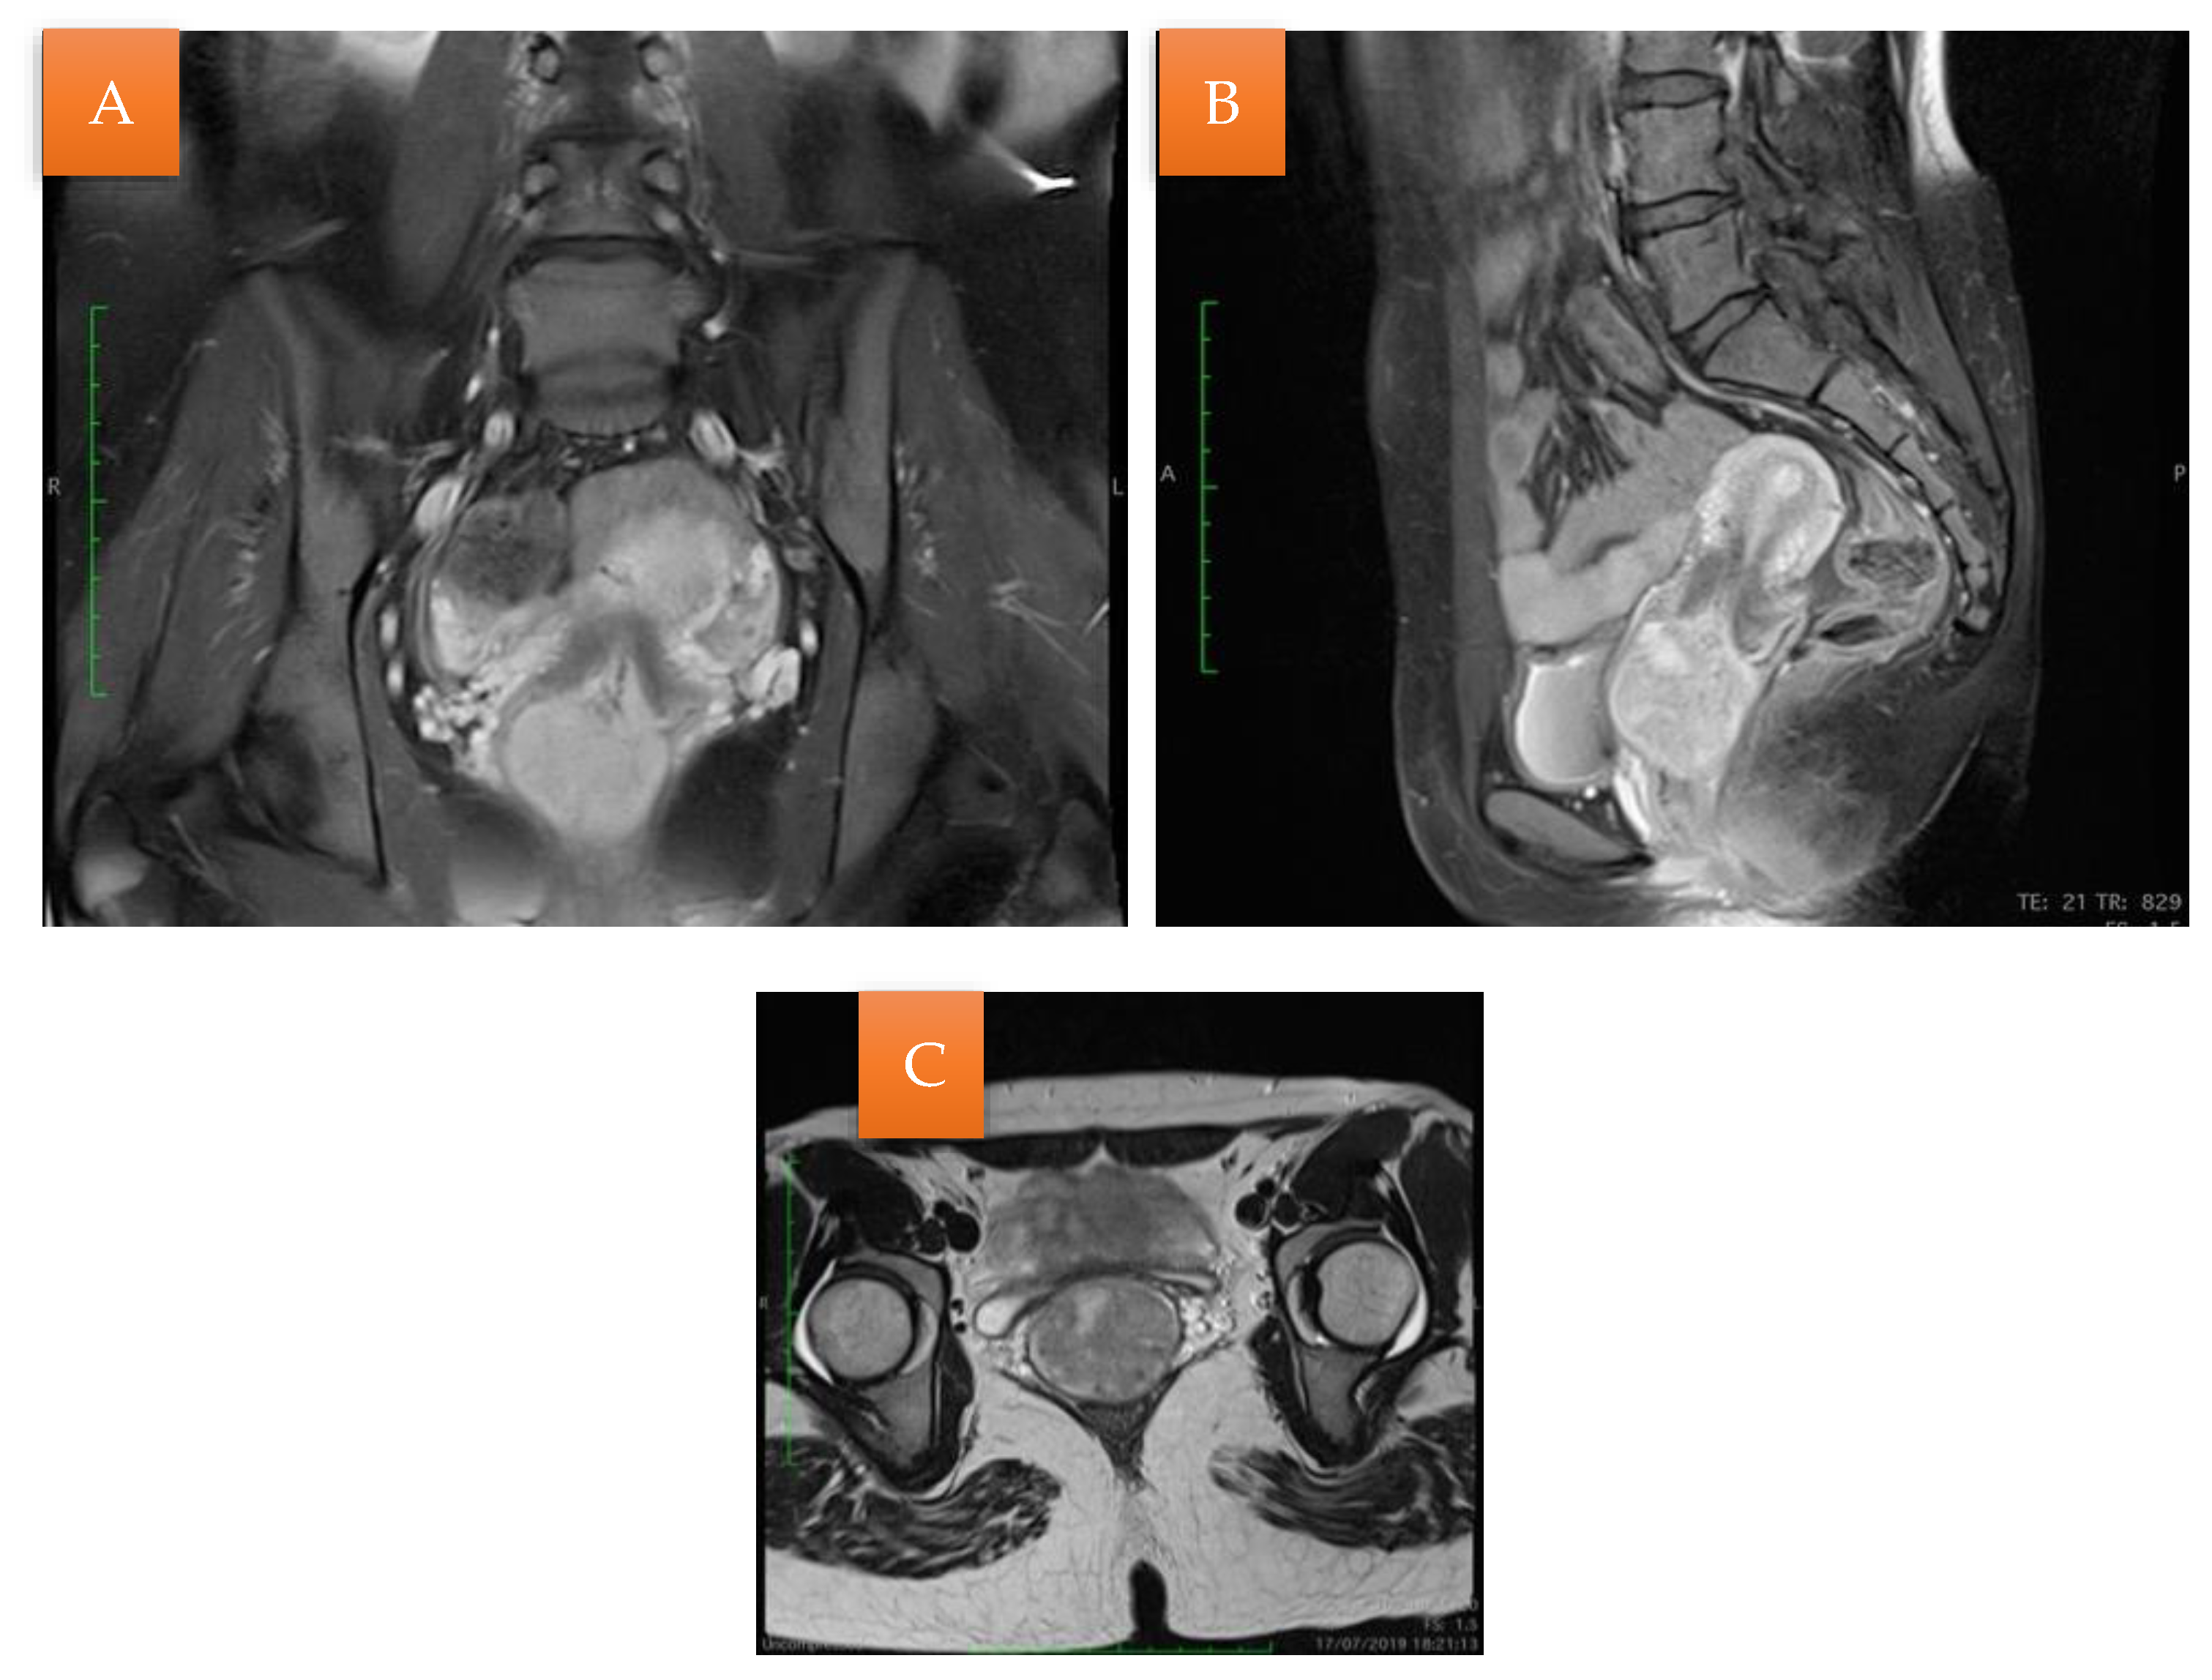

The histopathological exam revealed the tissue fragments to be sufficiently delimited by a thin layer of the endometrium composed of a biphasic stromal and glandular proliferation and represented by cellular stroma with edematous areas with thin blood vessels interspersed with thick bundles of smooth muscular fibers that included irregularly contoured secretory endometrial glands (Figure 4 and Figure 5), organized in hyperplastic lobular areas, and lined by the simple and pseudostratified epithelium with hyperchromatic nuclei (Figure 6), eosinophilic metaplasia, and a tendency for squamous differentiation.

Our microscopic findings are consistent with the following histopathological characteristics that define the atypical polypoid adenomyoma: a well-circumscribed biphasic tumor composed of endometrioid glands with a complex or lobular histoarchitecture, squamous morular metaplasia, and sometimes cytologic atypia, interspersed with a fibromyomatous stroma, which may present myxoid change.

Figure 4. Endometrial glands with lymphoid follicles and associated smooth muscle fibers (HE × 10).